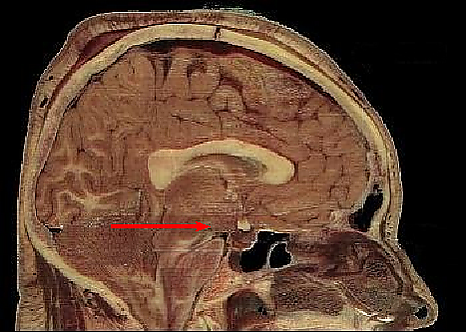

Гипоталамус является частью промежуточного мозга. Он образует основание и стенки нижней части третьего желудочка. Название своё он получил от греч. гипо- (под, внизу) и таламос (чертог, спальня), так как он располагается под таламусом. Гипоталамус отделён от таламуса гипоталамической бороздой (лат. sulcus hypothalamicus). Анатомические границы гипоталамуса определены недостаточно чётко, что связано с тем, что некоторые группы клеток заходят в соседние области, а также с некоторой неопределённостью в терминологии[3]. Считается, что спереди (рострально) гипоталамус ограничен терминальной пластинкой (лат. lamina terminalis), а его задняя (каудальная) граница — воображаемая линия от задней комиссуры (лат. commissura posterior) до каудальной поверхности сосцевидных тел. Дорсолатерально гипоталамус доходит до медиального края мозолистого тела[4].

В нижней части гипоталамуса выделяются такие структуры, как сосцевидные тела (лат. corpus mamillare), серый бугор (лат. tuber cinereum) и воронка (лат. infundibulum). Воронка отходит от серого бугра, средняя часть воронки приподнята и называется срединным возвышением (лат. eminentia mediana), которое в некоторых классификациях относят к серому бугру, а в некоторых — к нейрогипофизу[5]. Срединное возвышение содержит кровеносные сосуды, переносящие выделяемые гипоталамусом вещества в гипофиз. Нижняя часть воронки переходит в ножку гипофиза.